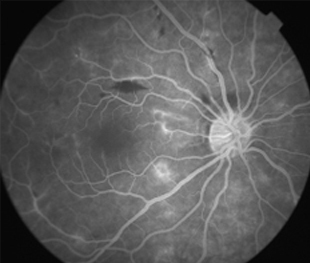

Angiografía OI

- Angiografía: teñido arterial, escape capilar, más tardíamente, no perfusion arteriolar y venular con teñido de las paredes vasculares y dilatación venosa.